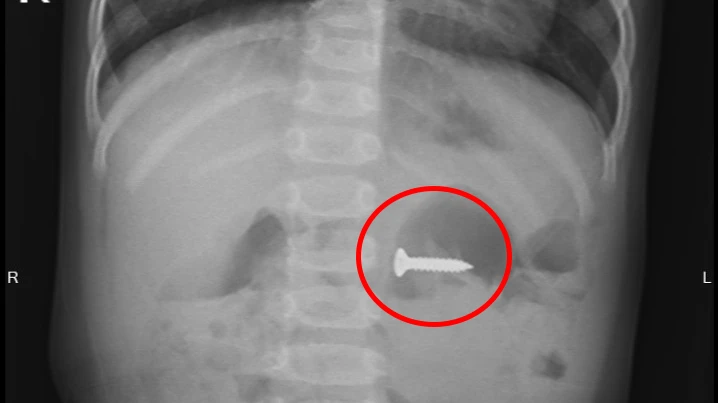

Ảnh chụp X-quang cho thấy chiếc đinh vít sắc nhọn đang nằm trong dạ dày cháu bé.

Từ mô tả của gia đình, bệnh viện đã cho chụp X-quang, phát hiện dị vật là chiếc đinh vít sắc nhọn, dài 2 cm, đang trong dạ dày cháu bé. Bác sĩ đã tiến hành gây mê nội soi đường tiêu hóa để gắp dị vật.